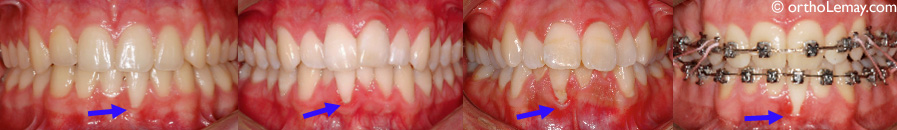

Quelques exemples de déchaussement de la gencive sur des incisives inférieures. Les cas les plus sévères sont dirigés au dentiste généraliste ou parodontiste pour évaluer la nécessité de faire une greffe gingivale ou autre procédure muco-gingivale. La présence de plaque dentaire et d’inflammation importante dans la région du déchaussement ne font qu’empirer le processus destructeur de la gencive et de l’os alvéolaire (parodonte).